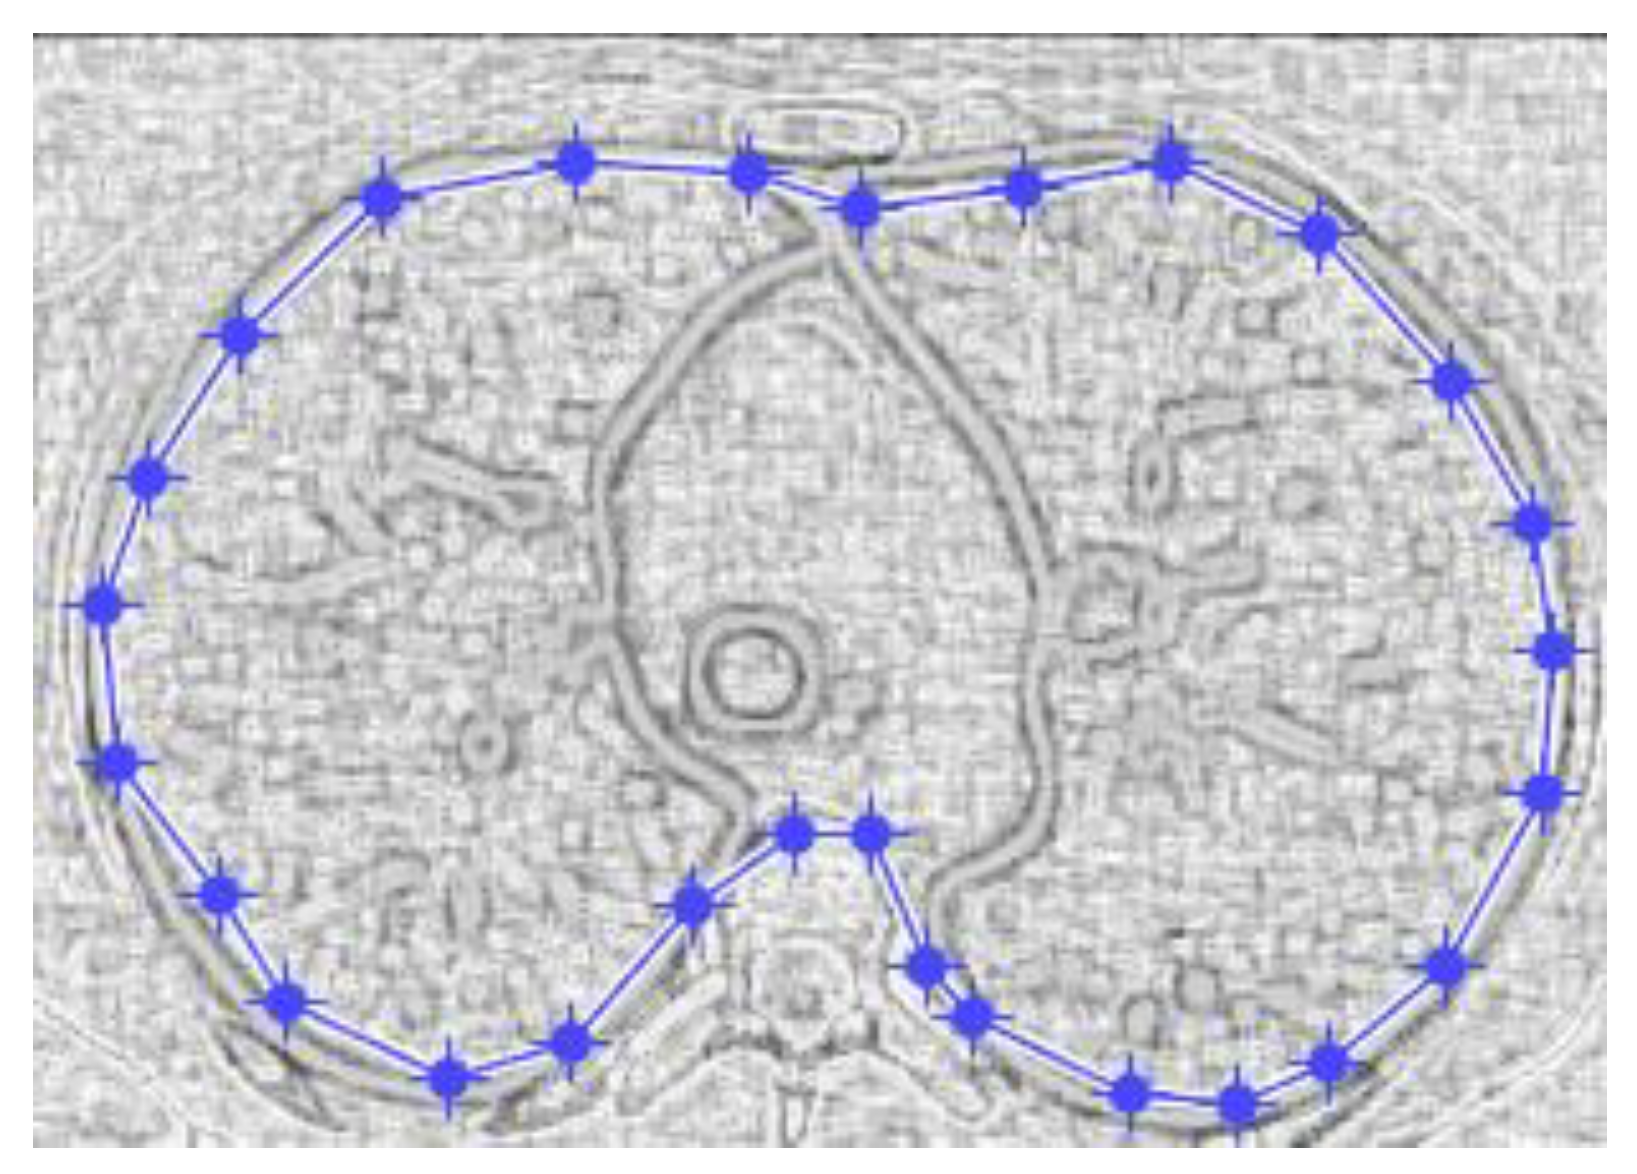

Figure 9 and Figure 10 show the original CT lung image, respectively, and the defined mask for the COVID-19 lung CT image, framed in a blue border in Figure 10.

Figure 10 presents the applied mask across the COVID-19 lung CT image, framed in a blue colour border.

Figure 10. Mask applied for COVID-19 lung image.